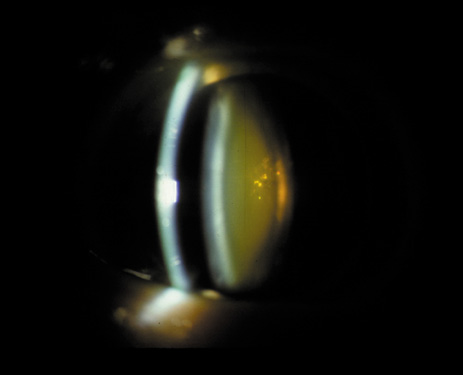

Nuclear cataracts tend to progress slowly. The refractive index of the lens changes as the nucleus progressively hardens, which usually results in increasing myopia.20,21 In some patients this is accompanied by optical distortion, especially of distant images, while near vision remains unaffected. A nuclear cataract is best seen with the narrow-beam direct illumination employed by the slit-lamp, which reveals the color and generalized haze or opalescence of the nucleus. In the early stages, the two halves (cotyledons) of the embryonic nucleus remain visible (Fig. 3). Later the entire nucleus appears as a homogeneous mass in contrast to the cortex (Fig. 4). Retroillumination may show the “oil droplet” effect (Fig. 5). Sometimes one may notice crystals in the lens nucleus (known as a Christmas tree cataract; Fig. 6A and B).

Fig. 3. Early nuclear cataract. Note the “cotyledons” in the nucleus.

Fig. 4. Advanced nuclear cataract. Note the homogeneous nuclear opacity.

Fig. 5. “Oil droplet” appearance of a pure nuclear cataract seen on retroillumination examination.